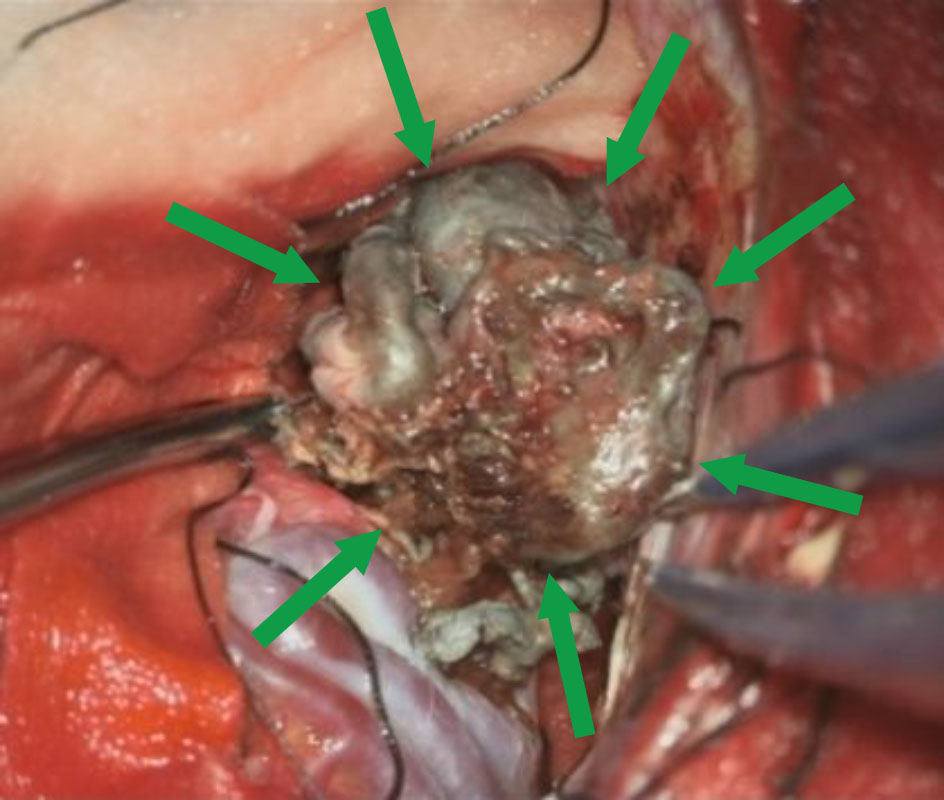

No.359 モニタリング

No.359 手術前

No.359 手術中

No.359 手術後

出血既往があり。2回の手術前血管内手術の後に、

Lateral transpeduncular approachにより再々出血予防を目的に

摘出手術を行う。完全摘出であることを確認した。

手術による合併症や後遺症なしで退院した。経過良好。